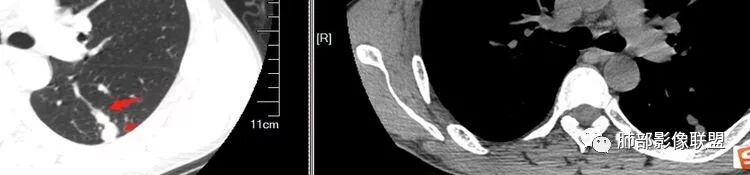

南边:问一个问题:支气管在这里堵了吗

Shelia:堵了,而且支气管壁增厚了。

Coke with ice:我认为堵了,不倾向于肿瘤的堵塞。对于这个病例来说,结核的爬行和肿瘤的堵塞鉴别点不清晰。

南边:这是支气管吗?

张立:是

南边:

远端有支气管显示,提示支气管局部没有堵塞,这个近端的看起来堵塞的支气管可能是假象。